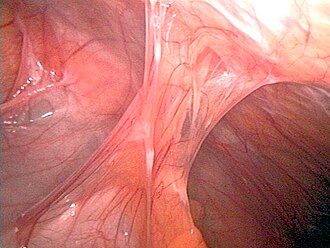

Adhesions after an appendectomyAdhesions after human appendectomy.

Hic et nunc Public Domain via Wikimedia Commons

Certain diseases can also contribute to bloat. Adhesions, hernias, abscesses and neoplasms can externally compress parts of intestinal tract (Quesensberry, et al. 2021).

Adhesions are bands of fibrous tissue that connect either two or more organs together or they may connect organs to the abdominal wall. These form as a response to tissue injury which may happen due to open abdominal surgery (such as a spay), or inflammation due to an infection somewhere in the abdominal cavity or the spread of cancer. If adhesions form around the bowel, the bands can twist, pull or clamp down on the intestine like a vise. Abscesses, inflammatory lesions, and tumors can cause an obstruction anywhere in the GI tract (Harcourt-Brown 2002).